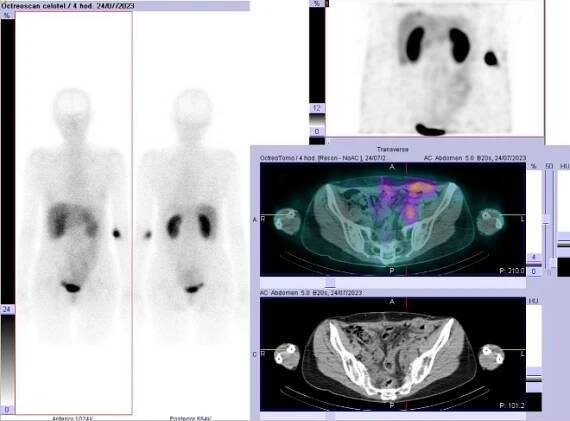

Obr. č. 1: Celotělová scintigrafie v přední a zadní projekci a SPECT/CT břicha a pánve 4 hod. po aplikaci OctreoScanu.